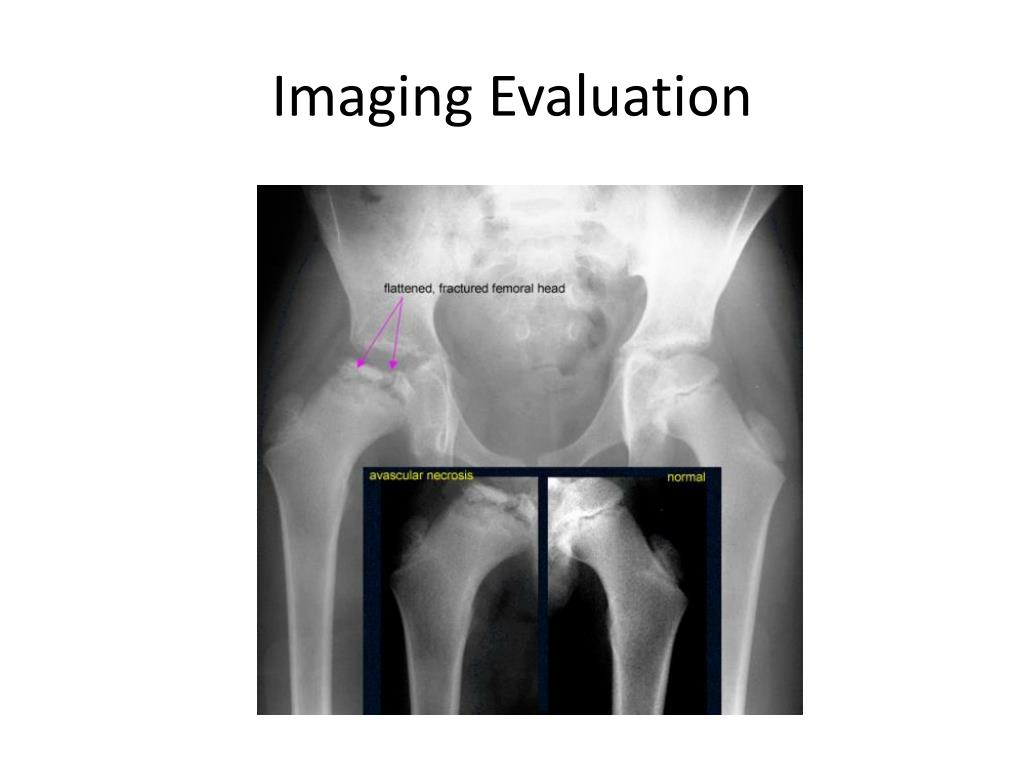

15. Imaging Evaluation

16. Imaging Evaluation

18. Imaging Evaluation • MRI • Bone scan • Arthrography • X-ray